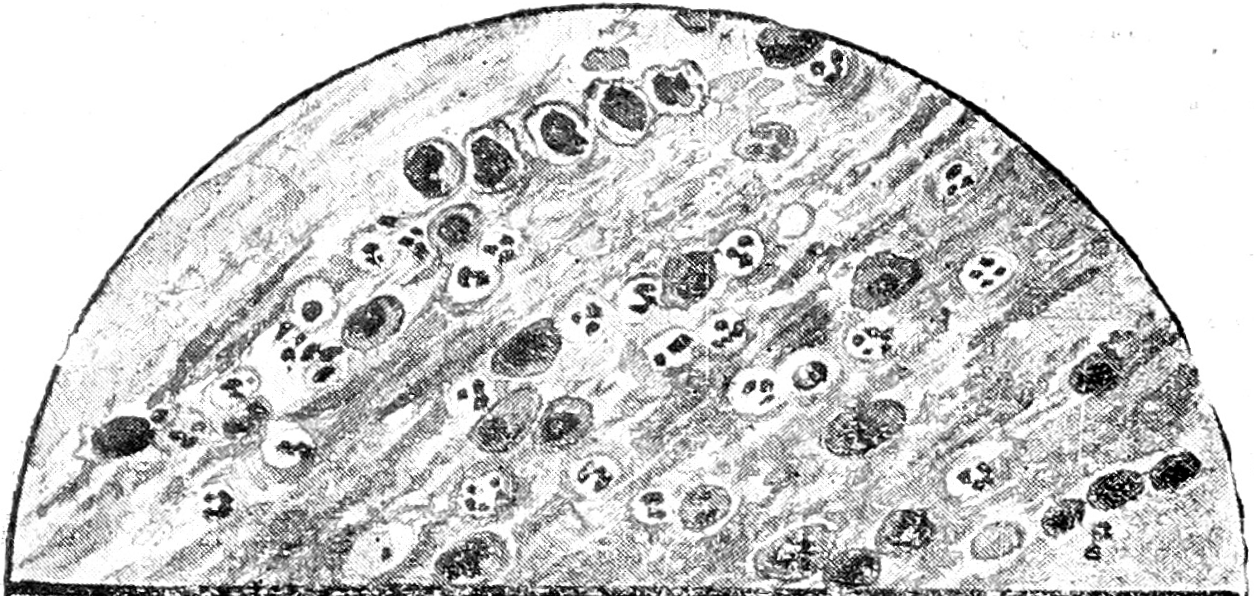

Рис. 2. Крупозная пнеймония на высоте заболевания. Фон мазка слизистый, N, большое количество МП, единичные Е.

Рис. 3. Крупозная пнеймония в стадии разрешения. Фон слизистый, N, большое количество МП, АМ.

В соответствии с макроскопическими изменениями мокроты при крупозной пнеймонии мы могли подметить строгую закономерность и в чередовании цитологических картин ее. Ржавая мокрота, обусловленная гиперэмией и пропотеванием в альвеолы плазмы крови и одновременным острым катарральным состоянием бронхов, давала под микроскопом яркую картину сплошного слизистого фона, местами перемежавшегося с очагами выпотевшего белка; на этом фоне встречалось иногда значительное количество эритроцитов, небольшое число лейкоцитов и изредка единичные моноцитоподобные клетки.

В стадии красной гепатизации число красных телец постепенно уменьшалось вплоть до полного исчезновения, зато резко увеличивалось число моноцитоподобных элементов и лейкоцитов, и появлялись AM. В дальнейшем, с переходом мокроты в гнойно-слизистую и слизистую, эритроциты совершенно исчезали, моноцитоподобные элементы постепенно уменьшались в числе, число же лейкоцитов, напротив, увеличивалось, как и число AM, а фон мокроты из сплошного становился сетчатым. Эта картина обычно держалась все время разрешения, причем AM, наростая, иногда сплошь закрывали все поле зрения. Далее мокрота постепенно теряла вышеуказанные элементы и к моменту выздоровления приобретала бронхитический вид.